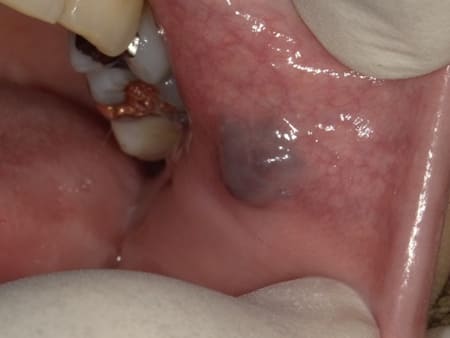

症例3 左側頬粘膜の血管腫(50歳代 女性)

以前よりあった頬粘膜の腫瘍が少し大きくなった感じがあるとのことで、来院されました。弾性軟の暗紫色の腫瘍であり圧迫により退色反応があることから頬粘膜血管腫と診断して摘出術を施行しました。